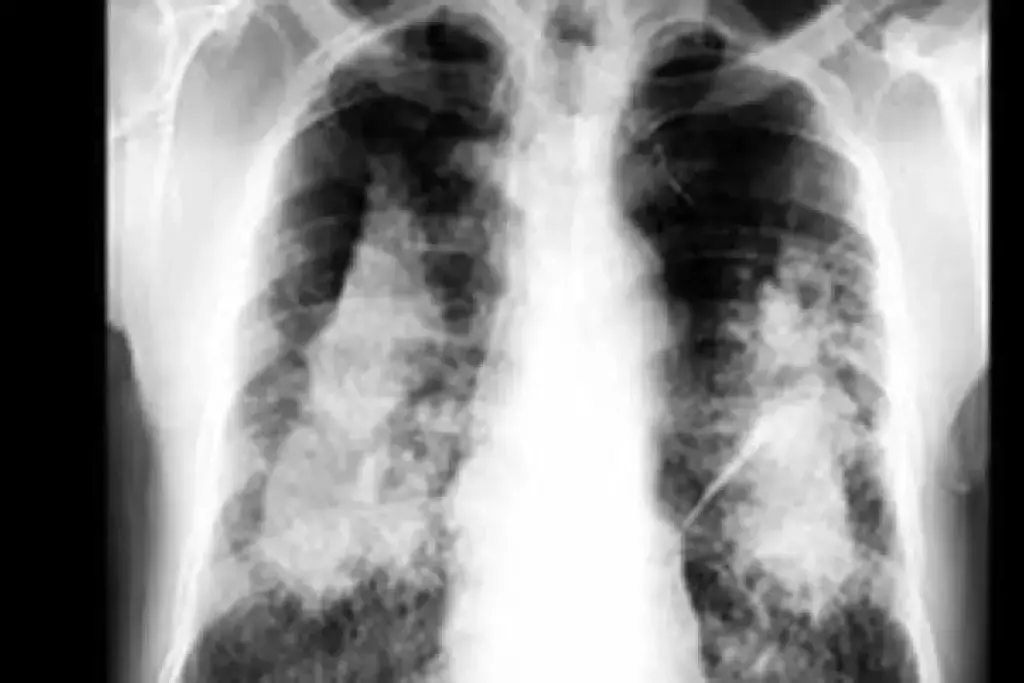

Stage 4 pulmonary fibrosis is the most severe stage of idiopathic pulmonary fibrosis (IPF). At this point, lung function is greatly reduced. The disease has caused a lot of scarring and damage to the lung tissue.

Advanced lung fibrosis, or stage 4 IPF, is marked by a lot of scarring in the lungs. This makes it hard for the lungs to exchange gases. As a result, there’s not enough oxygen in the blood, known as hypoxemia. People at this stage often have severe breathing problems, which really affects their life quality.

The journey of idiopathic pulmonary fibrosis through its stages is complex. It starts with mild symptoms and gets worse over time, ending at stage 4. As the disease progresses, more lung tissue gets scarred, leading to a decrease in lung function.